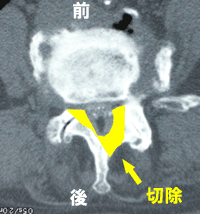

椎弓切除1

B.椎弓切除1

実際には椎弓と、必要に応じて椎間関節の一部を削って、脊柱管を

広げます(右図Bの黄色い部分)。ところが、狭窄が強い場合、ある